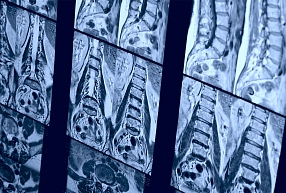

Sāpes mugurā un locītavās ir viena no mūsdienu sabiedrības veselības un medicīnas aktuālākajām problēmām. Muguras un ekstremitāšu sāpes ierobežo pacientu spējas veikt ikdienas mājas darbus, ierobežo spējas pildīt darba pienākumus, rada atkarību no pretsāpju medikamentiem. Muguras un ekstremitāšu sāpju iemesli var būt dažādi.

Mēs specializējamies:

• vertebroloģijā

• ortopēdijā

• kaulu, locītavu slimību ārstēšanā

• muguras sāpju ārstēšanā

• mugurkaula ķirurģijā

• algoloģijā

Veicam sāpju iemesla diagnostiku, piedāvājam ārstēšanu un dažādus palīglīdzekļus, kas palīdz novērst locītavu un muguras sāpes.